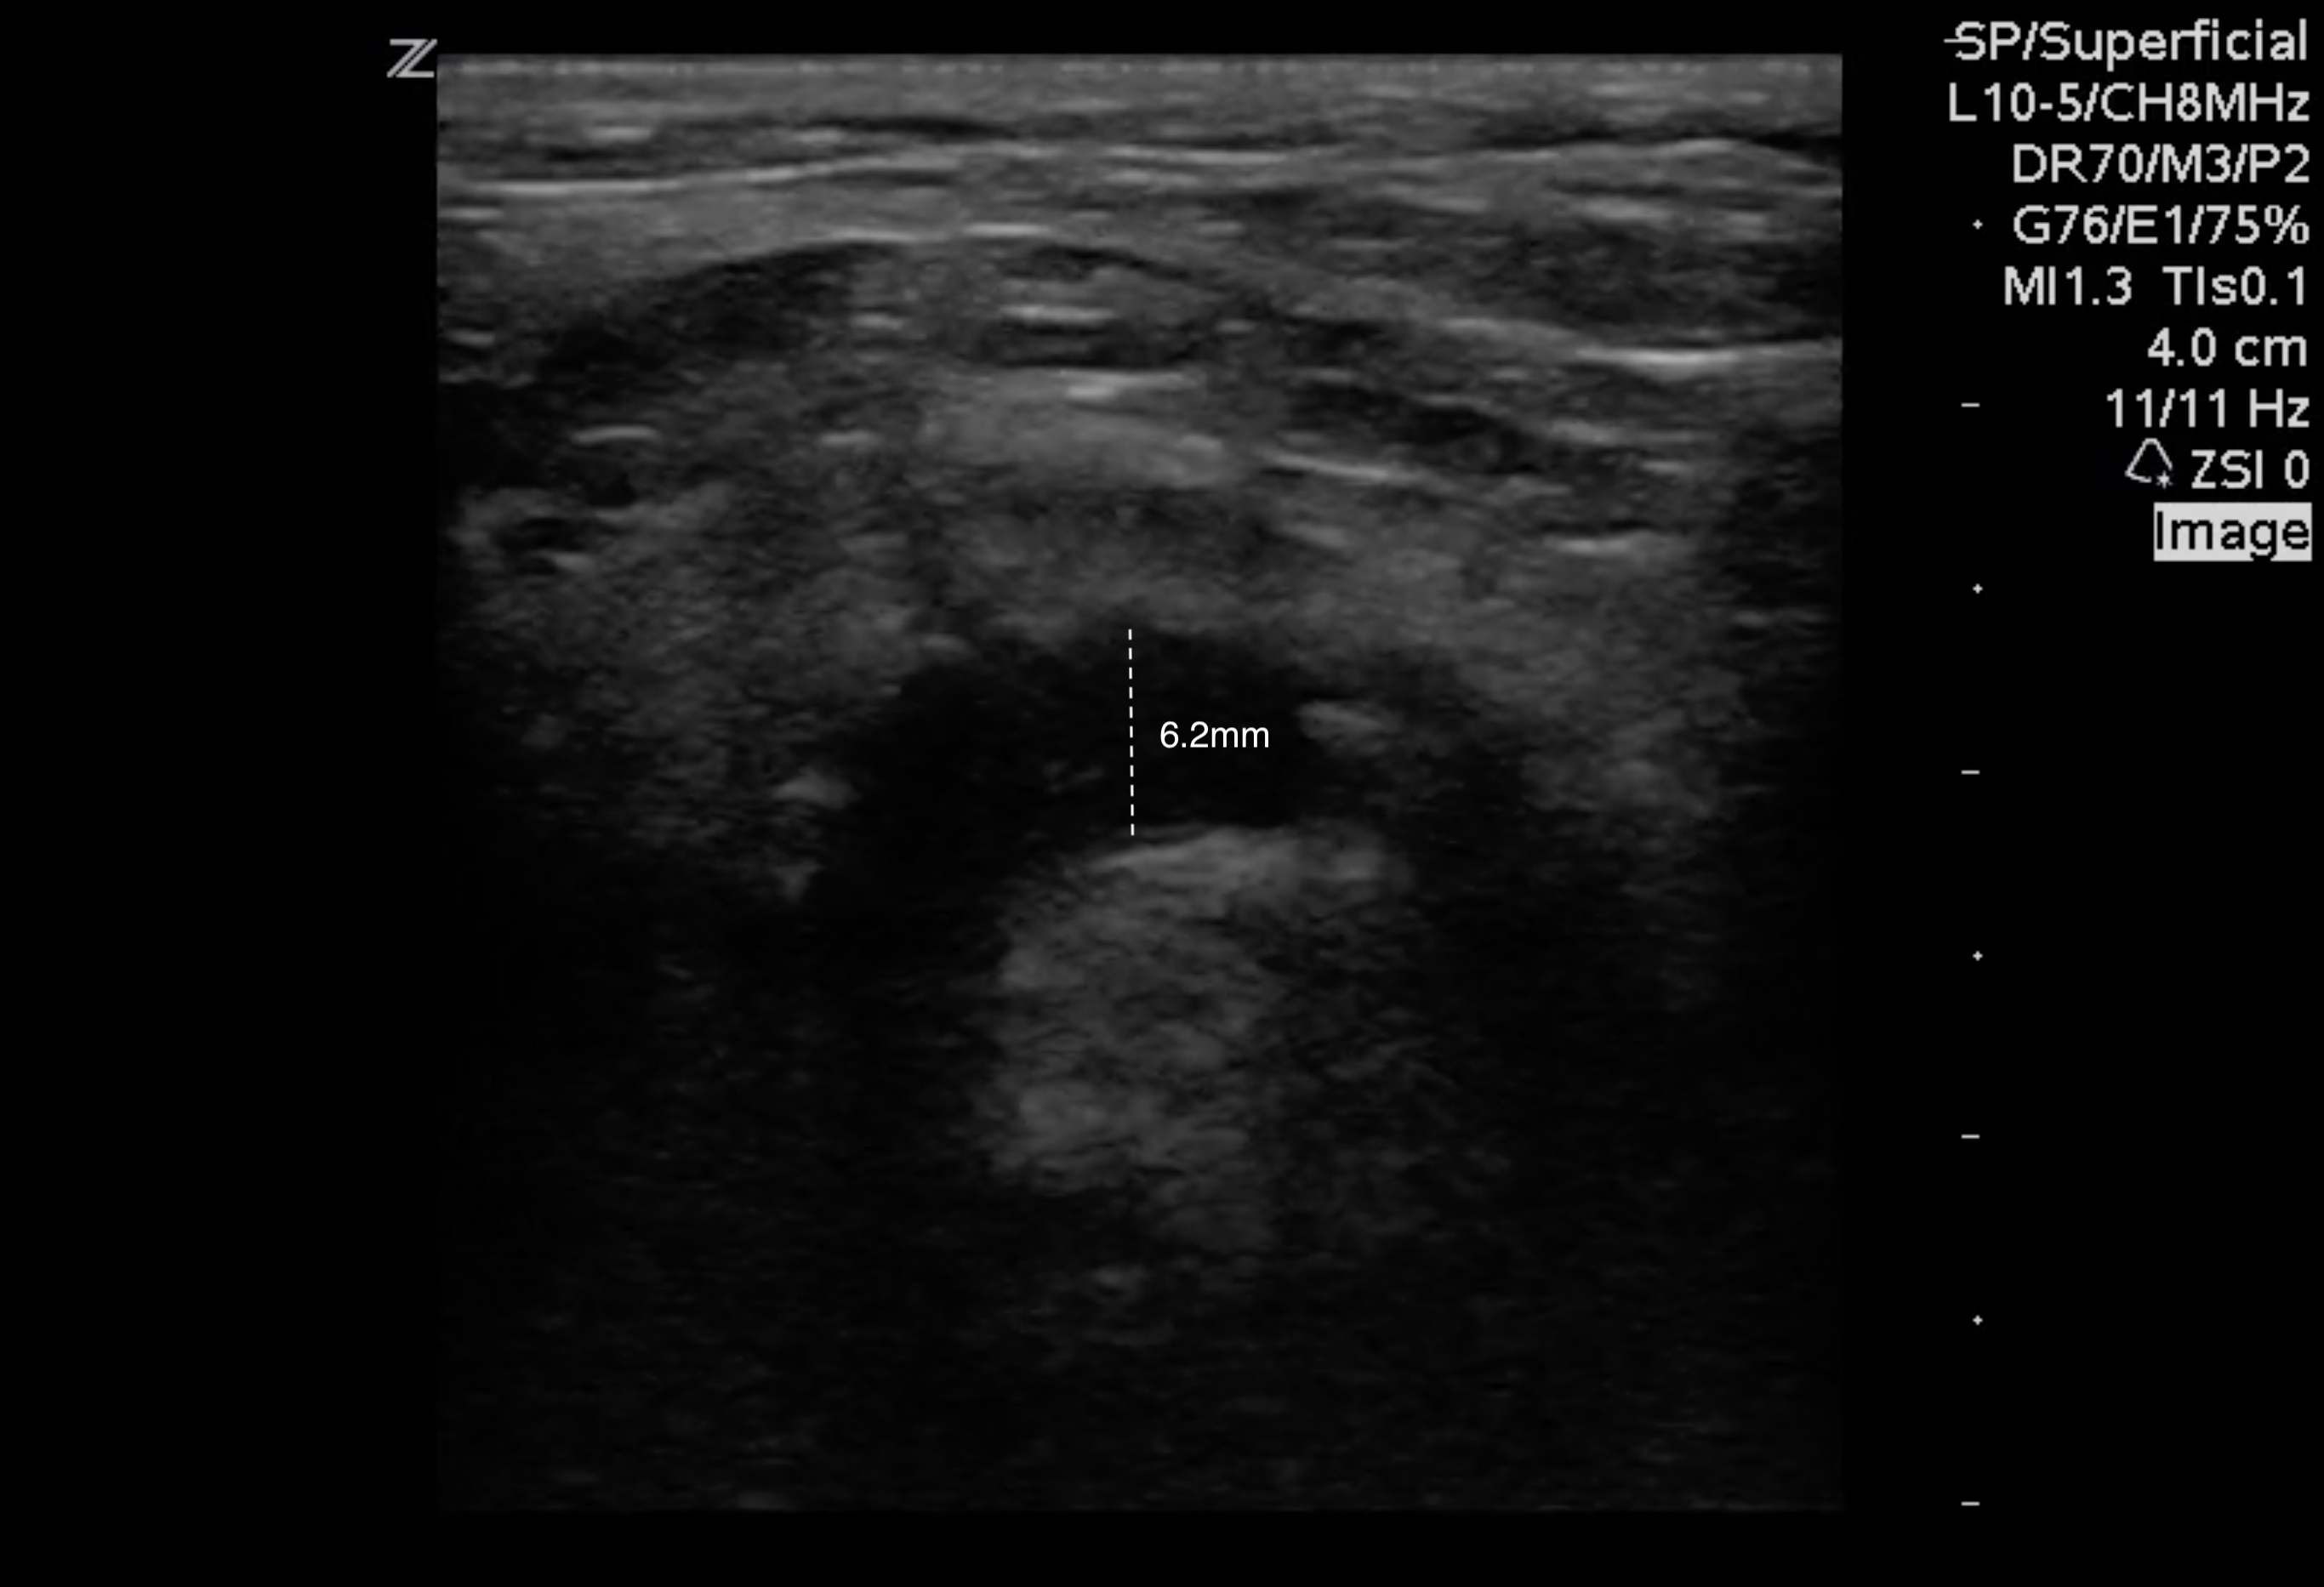

- On bedside ultrasound, the upper limit of normal for the anterior-posterior diameter of the epiglottis is 3mm.3

- Figure 8. This epiglottis measured 6.2mm in the anterior-posterior aspect.